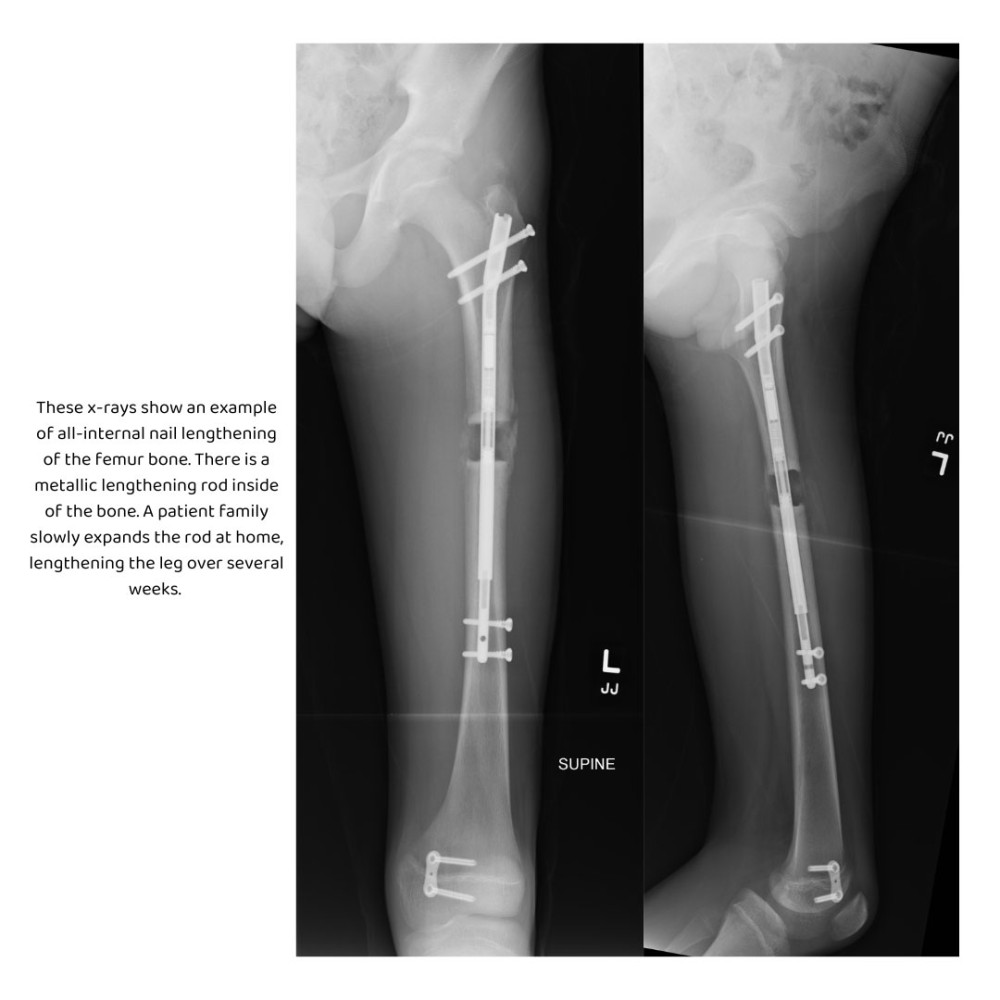

These x-rays show an example of all-internal nail lengthening of the femur bone. There is a metallic lengthening rod inside of the bone. A patient family slowly expands the rod at home, lengthening the leg over several weeks.